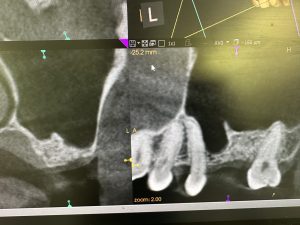

隔壁があり、難儀なデンサーリフトだったが、デンサーバーならではのリフティング💪

非常に良く安定している💪

今時、人工骨なんか使うは❌異物は洞内に入れない!